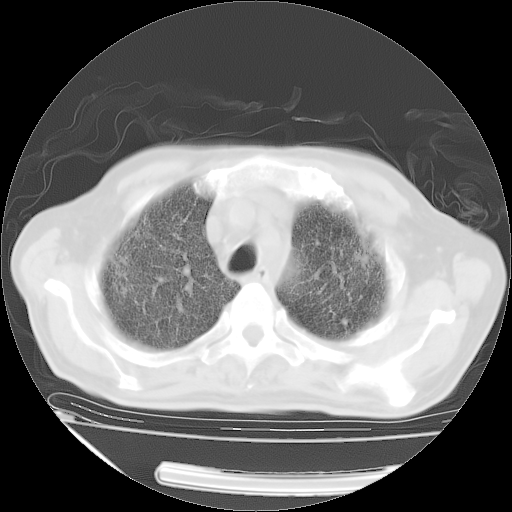

经过24天治疗,岳父的病情基本稳定。生活基本可以自理,可以下床活动。呼吸困难早已消失。体温基本正常。

只是甲强龙用80mg时血小板升到正常,改为60mg后又降到63×10*9/L。

主要治疗甲强龙80mg×14天,60mg×10天;同时抗结核(异烟肼+利福平+乙胺丁醇)。环磷酰胺0.1 tid 10天。

特别感谢胡教授、高管、桃子版主给出关键的治疗建议。桃版把所有肺部影像和全部临床资料请所在医院呼吸科、感染病科、结核科、临床免疫科专家会诊。临床免疫科专家制定了完整的治疗方案。